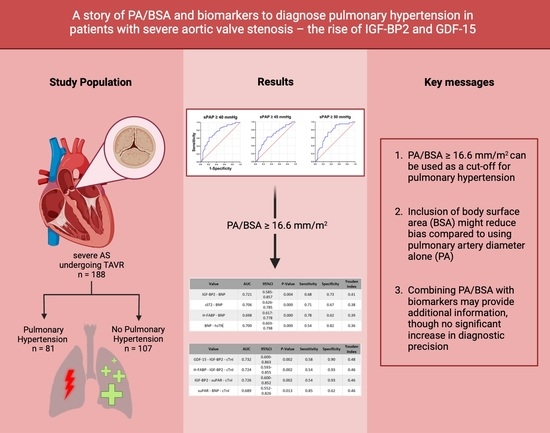

A Story of PA/BSA and Biomarkers to Diagnose Pulmonary Hypertension in Patients with Severe Aortic Valve Stenosis—The Rise of IGF-BP2 and GDF-15

Abstract

2. Materials and Methods

3. Results

4.1. Can a PA/BSA ≥ 16.6 mm/m2 Be Used as Evidence for PH?

4.3. Can a PA/BSA ≥ 16.6 mm/m2 Be Used Together with Biomarkers to Gain Additional Information?

5. Conclusions